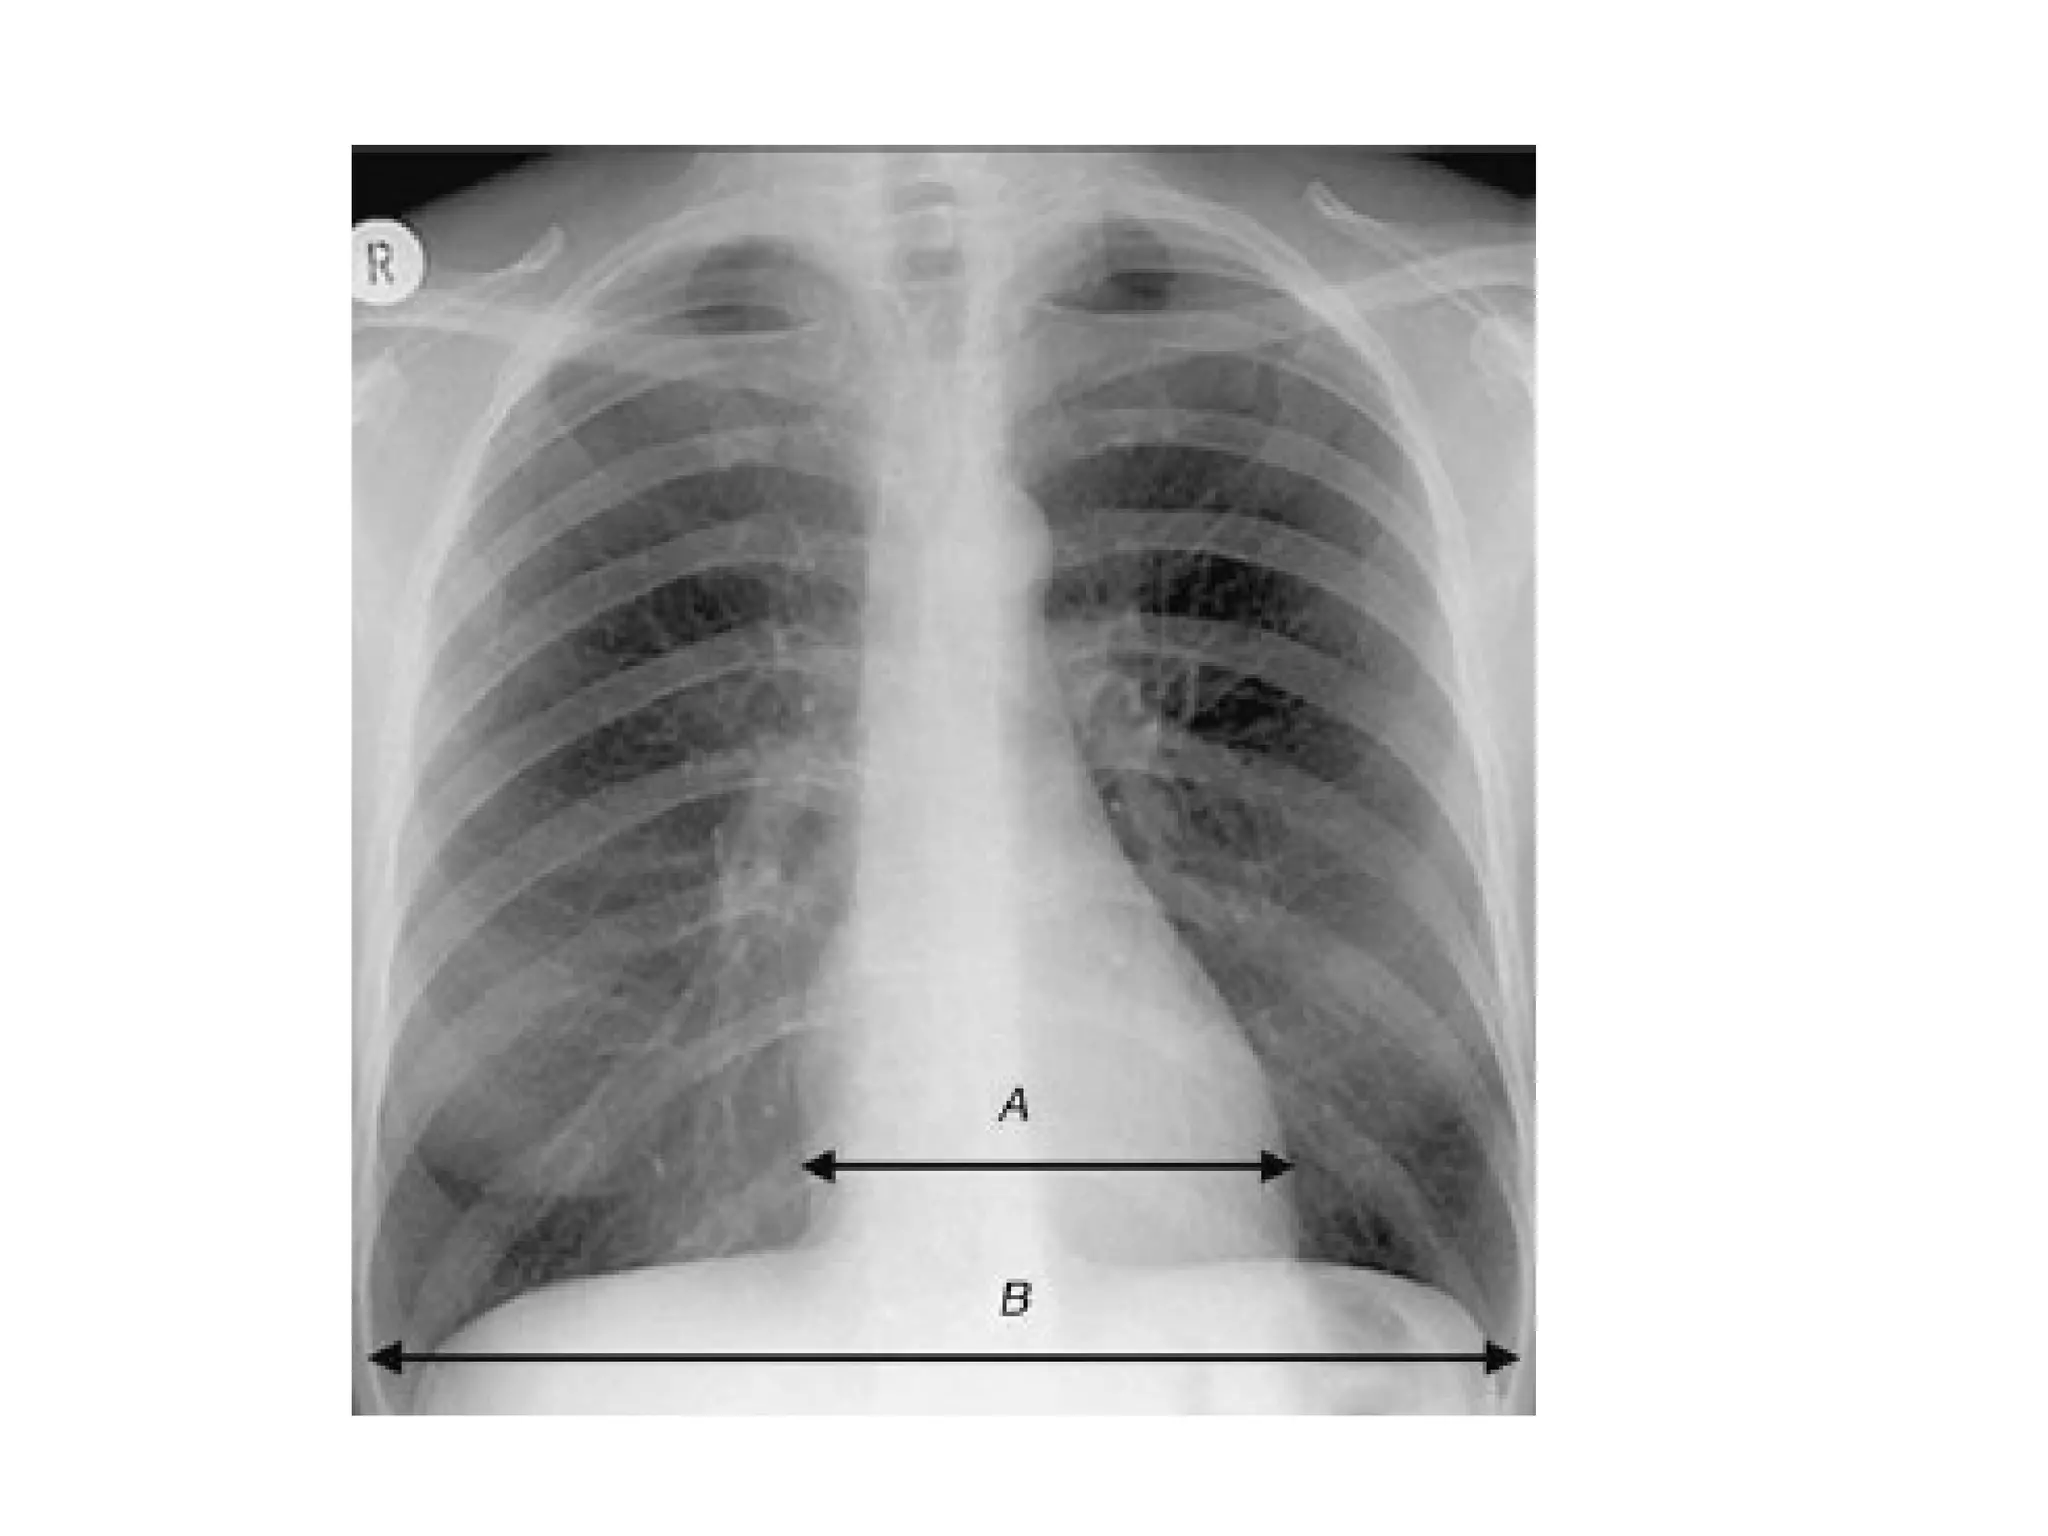

The mediastinum and heart

The central dense shadow seen on PA CXR

comprises the mediastinum, heart, spine and

sternum

The cardiac shadow lies to the left of the midline

and 1/3 to the right although it is quite variable

The transverse cardiac diameter normal for female

< 14.5 cm and for males < 15.5 cm.

The normal cardiothoracic ratio is < 50% on PA

film and < 60% in AP film.

An increase in excess of 1.5 cm in the transverse

diameter on comparable serial films is

significant.

The mediastinum andheart The central dense shadow seen on PA CXR comprises the mediastinum, heart, spine and sternum The cardiac shadow lies to the left of the midline and 1/3 to the right although it is quite variable The transverse cardiac diameter normal for female < 14.5 cm and for males < 15.5 cm. The normal cardiothoracic ratio is < 50% on PA film and < 60% in AP film. An increase in excess of 1.5 cm in the transverse diameter on comparable serial films is significant.